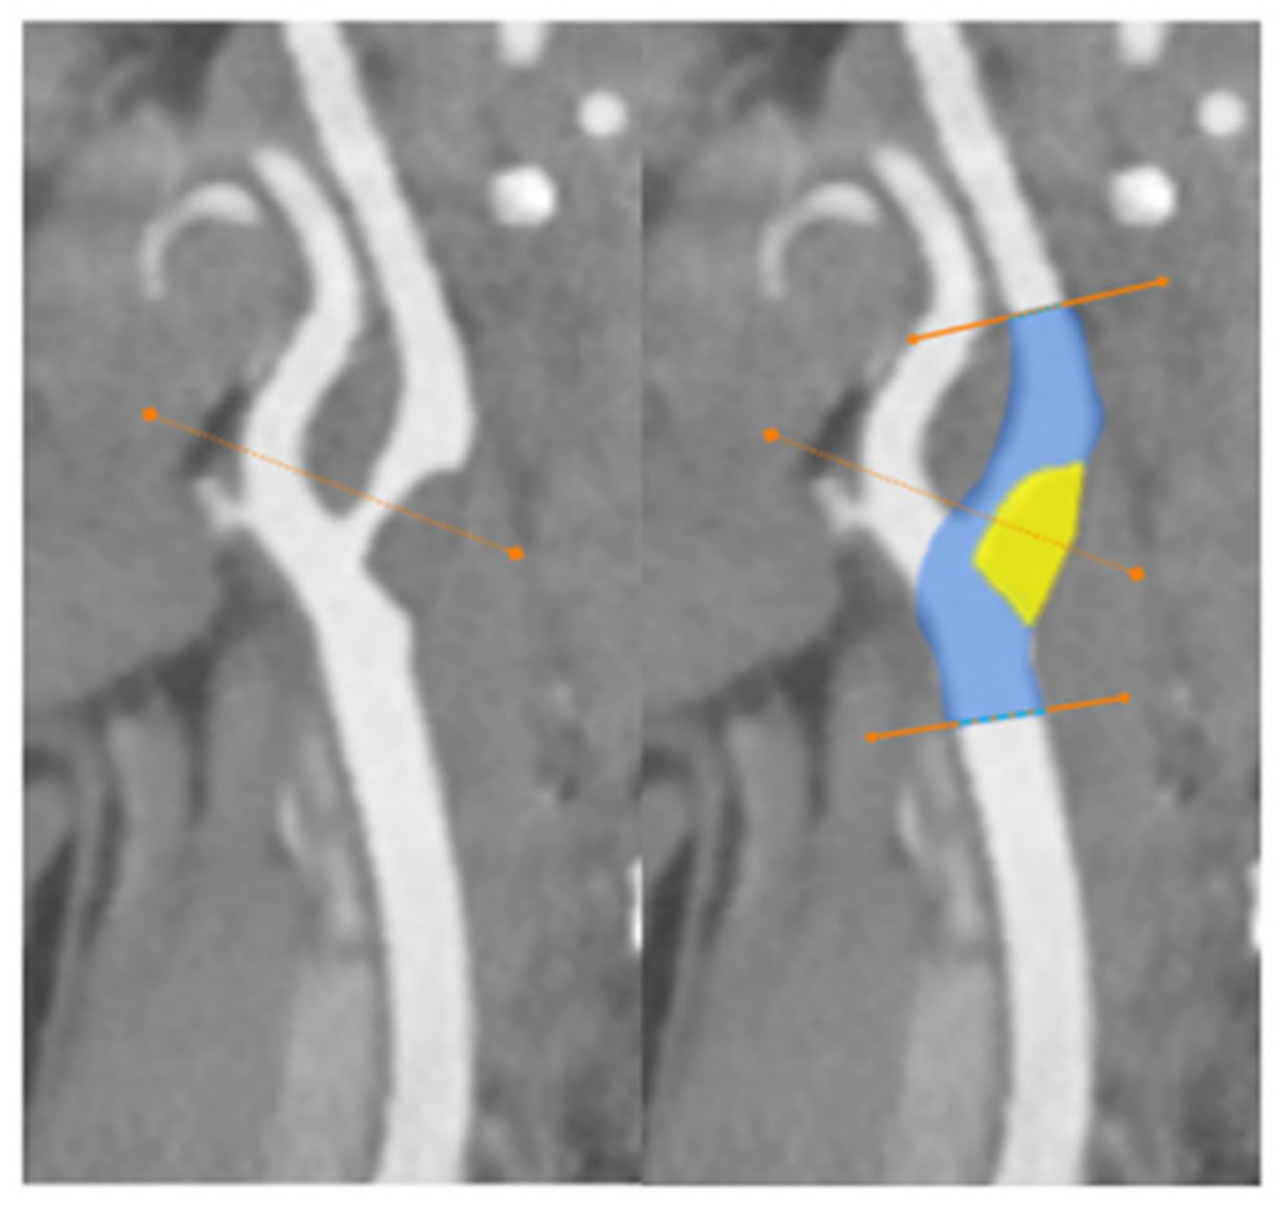

- Wang, A.; Mandigo, G.K.; Yim, P.D.; Meyers, P.M.; LaVine, S.D. Stroke and mechanical thrombectomy in patients with COVID-19: Technical observations and patient characteristics. J. NeuroInterv. Surg. 2020, 12, 648–653. [Google Scholar] [CrossRef]

- Viguier, A.; Delamarre, L.; Duplantier, J.; Olivot, J.-M.; Bonneville, F. Acute ischemic stroke complicating common carotid artery thrombosis during a severe COVID-19 infection. J. Neuroradiol. 2020, 47, 393–394. [Google Scholar] [CrossRef]

- Fara, M.G.; Stein, L.K.; Skliut, M.; Morgello, S.; Fifi, J.T.; Dhamoon, M.S. Macrothrombosis and stroke in patients with mild Covid-19 infection. J. Thromb. Haemost. 2020, 18, 2031–2033. [Google Scholar] [CrossRef]